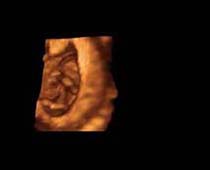

- صور لوجه الجنين في داخل الرحم

- صور جانبية لرأس الجنين

- صور للجنين في المراحل الأولى من الحمل

صور لأجنة ثلاثية الأبعاد بجهاز الموجات فوق صوتية | الدكتور نجيب ليوس